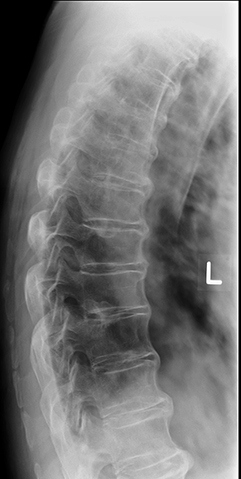

SI joint inflammation → fusion → ascends spine → complete spinal fusion (“bamboo spine”).

Radiographic signs of AS?

Early: SI joint blurring, narrowing; Late: “bamboo spine,” squared vertebrae.